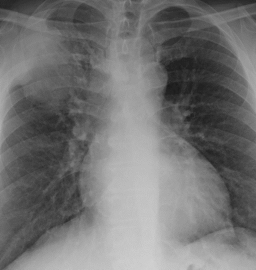

On exam, he had clearly reproducible point tenderness in his anterior right chest wall. Given this was his third visit for the same complaint, his risk factors, and his concerns, we decided to obtain laboratory studies and a chest x-ray.

His EKG was non-ischemic and his labs were unremarkable. However, his chest x-ray demonstrated a large mass in his right upper lobe. I quickly pulled up an old chest x-ray for comparison, he had small pulmonary nodule in the same spot a few years ago.

Given the now likely diagnosis of cancer, we decide to order a CT scan to further evaluate the mass. The CT showed a lesion consistent with primary lung cancer with local spread, causing a pathologic rib fracture – right at the spot where he had point tender musculoskeletal chest pain.